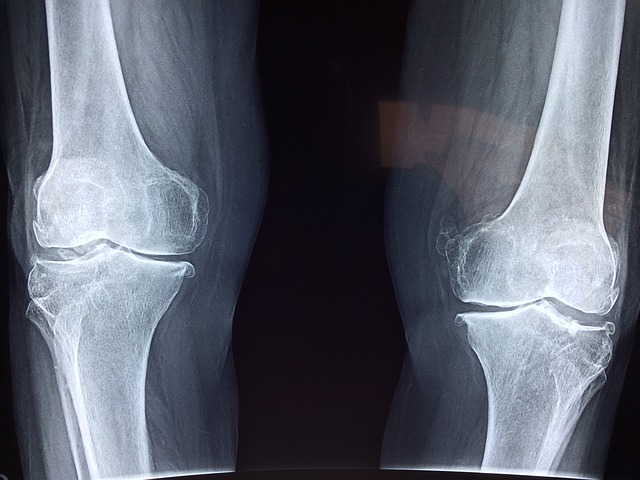

관절염은 관절의 염증과 통증을 동반하는 만성적인 질환으로, 예방과 적절한 관리를 통해 건강한 관절을 유지할 수 있습니다. 이제 관절염의 예방과 관리법, 그리고 자가치료법에 대해 자세히 알아보겠습니다.